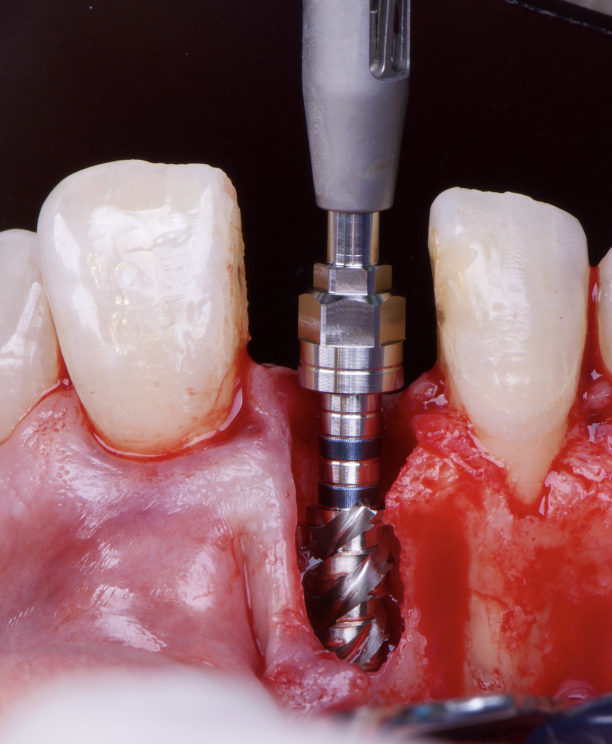

The surgical protocol began with the atraumatic extraction of tooth 1.1 to preserve as much of the alveolar socket as possible. Immediately following extraction, an N1 implant was placed into the socket using a guided surgical approach to ensure ideal three-dimensional positioning. The “one abutment one time” technique was applied to minimize soft tissue manipulation during the healing phase, which is particularly important in esthetic areas.

Given the significant buccal defect, guided bone regeneration (GBR) was performed simultaneously. A mixture of autologous bone and creos™ xenogain™ was applied to the defect and covered with a resorbable creos™ membrane to restore ridge width and support the buccal contour. In addition, a connective tissue graft was harvested and placed in the vestibular region to increase the thickness of keratinized mucosa. This combined approach addressed both hard and soft tissue deficiencies, providing the biological foundation for a stable and esthetic outcome.